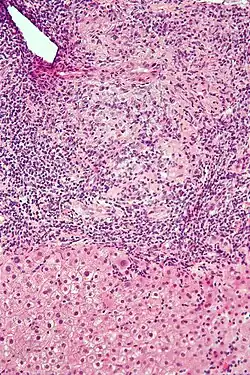

Micrograph of PBC showing bile duct inflammation and injury, H&E stain

On microscopic examination of liver biopsy specimens, PBC is characterized by chronic, nonsuppurative inflammation, which surrounds and destroys interlobular and septal bile ducts. These histopathologic findings in primary biliary cholangitis include:[32]

• Inflammation of the bile ducts, characterized by intraepithelial lymphocytes

• Periductal epithelioid granulomas.

• Proliferation of bile ductules

• Fibrosis (scarring)

The Ludwig and Scheuer scoring systems have historically been used to stratify four stages of PBC, with stage 4 indicating the presence of cirrhosis. In the new system of Nakanuma, the stage of disease is based on fibrosis, bile duct loss, and features of cholestasis, i.e. deposition of orcein-positive granules, whereas the grade of necroinflammatory activity is based on cholangitis and interface hepatitis. The accumulation of orcein-positive granules occurs evenly across the PBC liver, which means that staging using the Nakanuma system is more reliable regarding sampling variability.

• Stage 1 – portal stage: Normal-sized triads, portal inflammation, subtle bile duct damage: Granulomas are often detected in this stage.

• Stage 2 – periportal stage: Enlarged triads, periportal fibrosis and/or inflammation, typically characterized by the finding of a proliferation of small bile ducts

• Stage 3 – septal stage: Active and/or passive fibrous septa

• Stage 4 – biliary cirrhosis: Nodules present, garland or jigsaw puzzle pattern